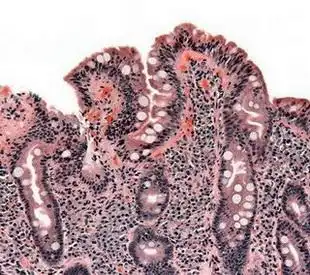

小肠绒毛的中心就是乳糜管

f 脂类 s 滑面内质网 g 高尔基复合体 c 乳糜微粒 cl 中央乳糜管

乳糜泻诊断